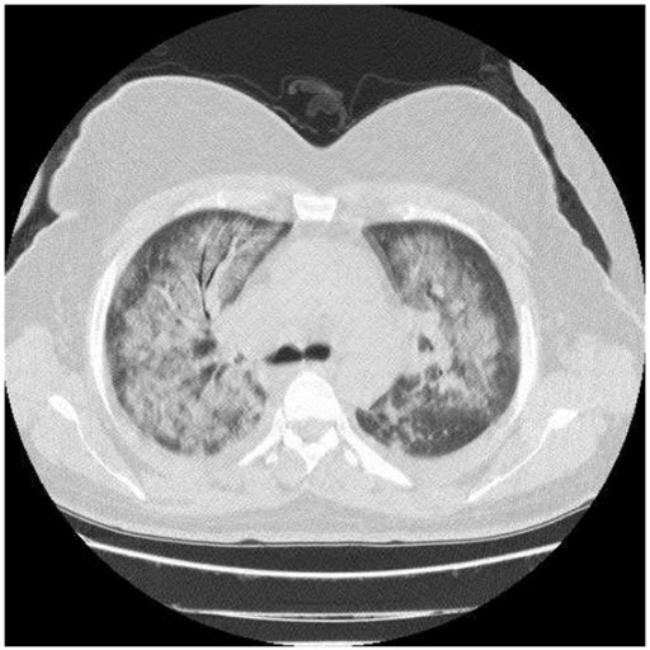

View Ards Ct Pictures. Introduction — acute respiratory distress syndrome (ards) is an acute, diffuse, inflammatory form of lung injury that is associated with a variety of etiologies. Definitions of acute lung injury (ali) and acute respiratory distress syndrome (ards) have varied over time.

Care guide for ards (acute respiratory distress syndrome). Definitions of acute lung injury (ali) and acute respiratory distress syndrome (ards) have varied over time. An expanded rationale, justification, and supplementary material.

Survey of german ards centers and scientific l. Ards can be life threatening. Acute respiratory distress syndrome (ards) is a rapidly progressive disease occurring in critically ill patients. Care guide for ards (acute respiratory distress syndrome).